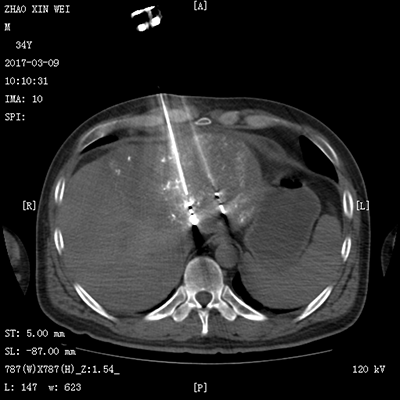

(肝癌的消融治療)(肺癌的消融治療)

(肝癌的粒子植入治療)(肺癌的粒子植入治療)

(骨惡性腫瘤的消融治療) (CT引導(dǎo)下骨水泥注射椎體成形術(shù)及粒子植入術(shù))